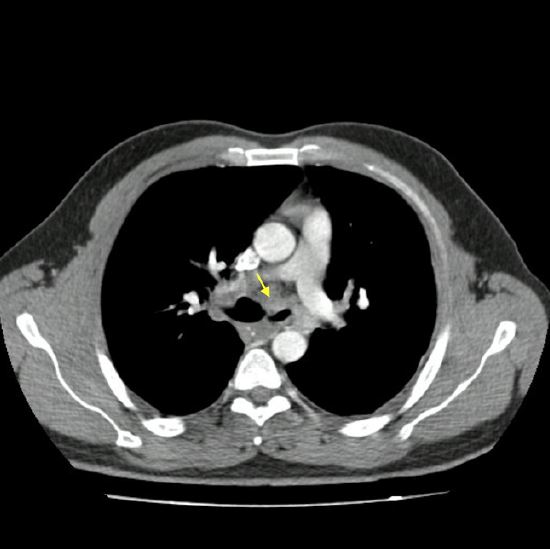

Ingresó a nuestra institución con una frecuencia cardiaca de 80 latidos/min, frecuencia respiratoria de 18 respiraciones/min, presión arterial en 118/76 mm Hg, temperatura de 36,5 ºC, saturación de oxígeno del 91% al ambiente; examen pulmonar normal y sin signos neurológicos. Los estudios iniciales revelaron un recuento de leucocitos de 7300/mm 3 con un recuento diferencial de linfocitos del 31% y neutrófilos del 54%, hematocrito del 31%, serología VIH negativa; así como función renal, electrolitos y pruebas de función hepática normales. Se realizó un nuevo TAC de control ( figura 1) que registró un aumento evidente en el tamaño de las linfadenopatías previamente descritas con evidencia de estrechamiento del bronquio principal izquierdo y nódulo subsólido izquierdo.